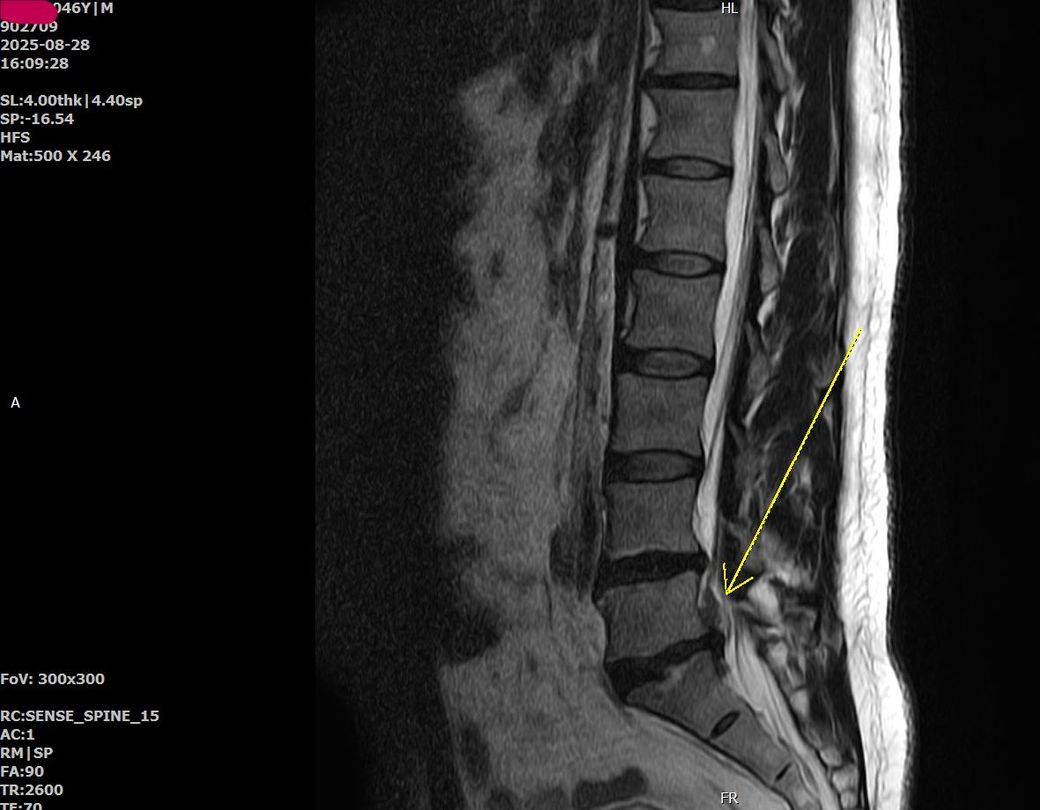

2.교통사고 상대(현대)과실0% 25/8/9부터~한의원~신경외과.재확의학과 치료중 진단서6장,< 허리척주원반의 와상성파열. 요추간판의 외상성파열>

첨에 한의원 진료를 2주정도받다가 허리가 너무 아퍼서 MRI찍어보니 4.5번이 삐져나와서 위아래로 텨져번져있더라구요

MRI영상 과 소견서 첨부요

• 영상과 판독지를 보면 외상성보다는 퇴행성으로 처리가 될 것으로 보입니다.

보험회사에서 14급이 아닌 12급으로 되어있을 것입니다. (외상성은 9급)